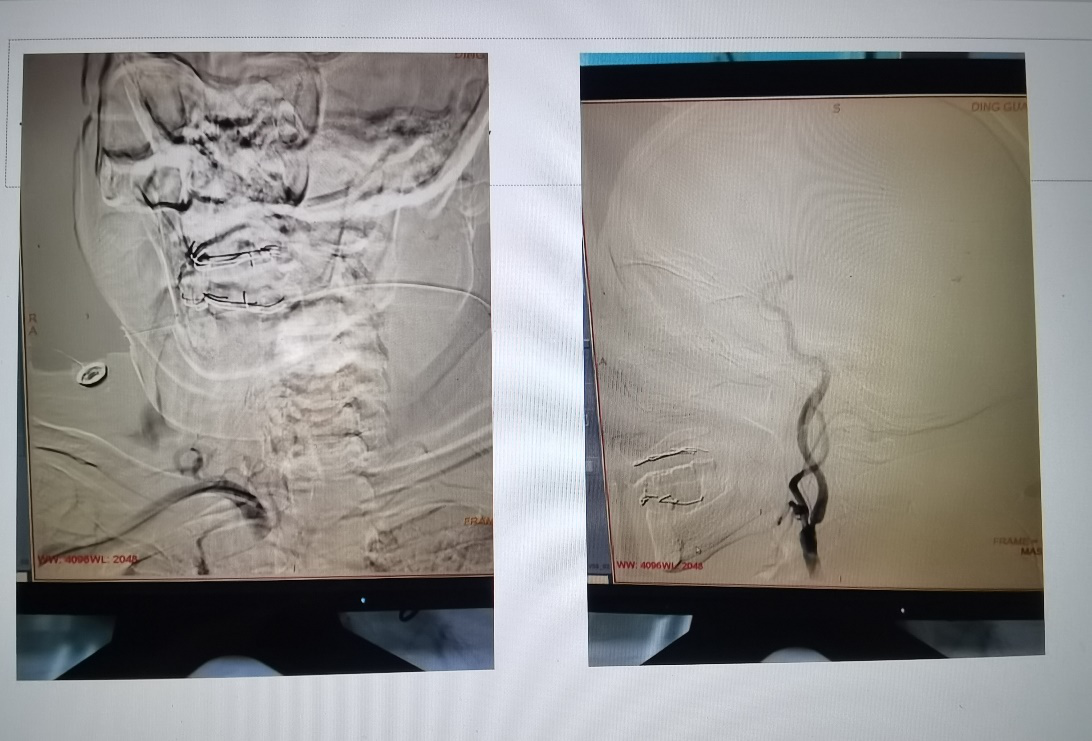

2022年7月12日,神经内科副主任徐永、医师丁会朋完成我院第一例经桡动脉全脑血管造影术。患者是一位77岁高龄男性,因反复头晕就诊我院神经内科,门诊行颈动脉超声提示左侧颈动脉中重度狭窄,为明确诊断及下一步治疗方案,收住神经内科行全脑血管造影检查。7月12日下午14点30分,手术开始,多次尝试股动脉置鞘,虽双侧股动脉穿刺均成功,但导丝无法顺利通过,考虑双侧股动脉粥样硬化狭窄。经全面评估后,决定经桡动脉穿刺完成手术。经桡动脉穿刺行全脑血管造影,所选造影材料不同于普通造影材料,操作困难,手术难度更大,经过约2小时的精心操作,在导管室和心内科的通力协作下,手术顺利完成。整台手术,患者神志清楚,无明显不适主诉,安返病房。经过造影评估,患者左侧颈内动脉起始段狭窄约70%,择期给予颈内动脉支架植入术。(徐永)